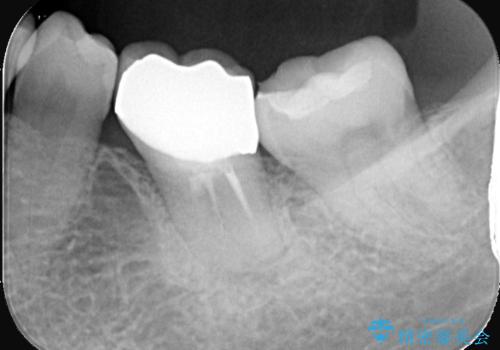

- 銀歯が取れたとのことで来院されました。中で虫歯が広がっている状態でした。材料の特徴を説明し、セラミックインレーでの修復となりました。

接着時にはラバーダム防湿を行いました。